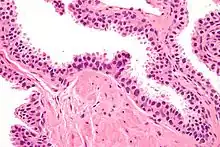

| Micrograph showing high-grade prostatic intraepithelial neoplasia. H&E stain. | |

High-grade prostatic intraepithelial neoplasia (HGPIN) is an abnormality of prostatic glands and believed to precede the development of prostate adenocarcinoma (the most common form of prostate cancer).[1][2]

Histology

Its cytologic features are that of prostatic adenocarcinoma:

- presence of nucleoli,

- increased nuclear-to-cytoplasmic ratio and,

- increased nuclear size.

Microscopically, PIN is a collection of irregular, atypical epithelial cells. The architecture of the glands and ducts remains normal. The epithelial cells proliferate and crowding results in a pseudo-multilayer appearance. They remain fully contained within a prostate acinus (the berry-shaped termination of a gland, where the secretion is produced) or duct. The latter can be demonstrated with special staining techniques (immunohistochemistry for cytokeratins) to identify the basal cells forming the supporting layer of the acinus. In prostate cancer, the abnormal cells spread beyond the boundaries of the acinus and form clusters without basal cells. In HGPIN, the basal cell layer is disrupted but present. PIN is primarily found in the peripheral zone of the prostate (75-80%), rarely in the transition zone (10-15%) and very rarely in the central zone (5%), a distribution that parallels the zonal distribution for prostate carcinoma.[7]

Several architectural variants of PIN have been described, and many cases have multiple patterns. The main ones are tufting, micropapillary, cribriform, and flat. Although these different appearances may cause confusion with other conditions, they have not been found to be of clinical importance. Rarer types are signet-ring-cell, small-cell-neuroendocrine, mucinous, foamy, inverted, and with squamous differentiation.[3]